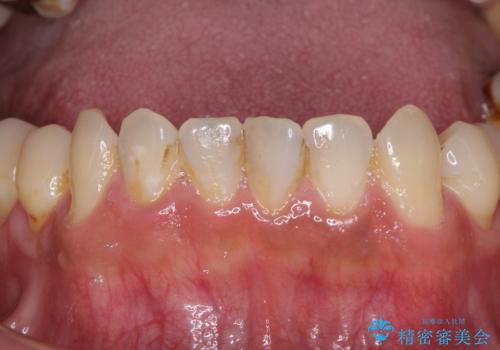

- 前歯や奥歯の虫歯を放置しており、それらの治療を契機に真っ白な歯にしたいとのことで来院された患者様です。

咬み合わせを改善するに当たって、抜歯しなければならない歯や歯列の改善が必要な箇所があったため、矯正治療やインプラント治療から始めていくこととしました。

不自然なくらい真っ白にしたいとのことでしたので、透明感のないフルジルコニアクラウンを用いて補綴することとしました。